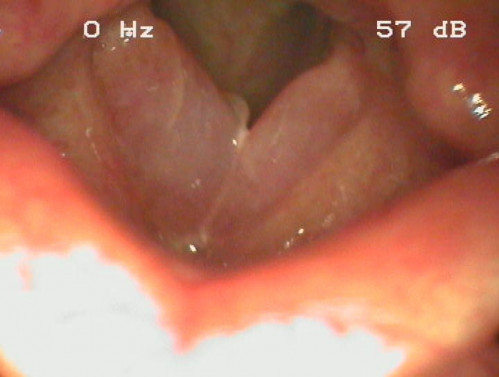

Raue, vertiefte mittlere Sprechstimme und zunehmende Heiserkeit

ICD: J38.4

Eine 47-jährige Frau beklagt eine zunehmend heisere Stimme. Die Patientin gibt außerdem an, seit ca. 30 Jahren 20 bis 40 Zigaretten pro Tag zu rauchen.

Im Anamnesegespräch fällt sofort die vertiefte mittlere Sprechstimmlage sowie eine Rauhigkeit der Stimme auf.